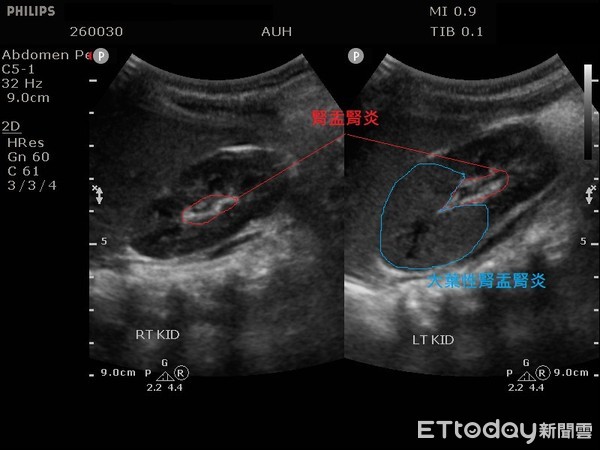

▲男嬰發燒5天患「急性腎炎」醫憂恐腎衰竭,圖為腎臟超音波。(圖/亞大醫院提供)

安排腎臟超音波檢查發現雙側腎盂腎炎及左腎前端實質發炎,留取尿液培養後確診為大腸桿菌引起的左側「急性大葉性腎盂腎炎」及雙側「急性腎盂腎炎」,經靜脈注射抗生素治療7天後,才順利出院,但因為大葉性腎盂腎炎為較嚴重的泌尿道感染,出院後仍需持續使用有效的抗生素治療三週以上。